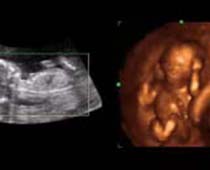

- Fetal Behavior Ultrasound Photos

- The Clinical Advantages of 3D and 4D Ultrasound

- Definition and Features of Four Dimensional Ultrasound

- Uses of 4D Ultrasound scan

- Fetal behavior during pregnancy